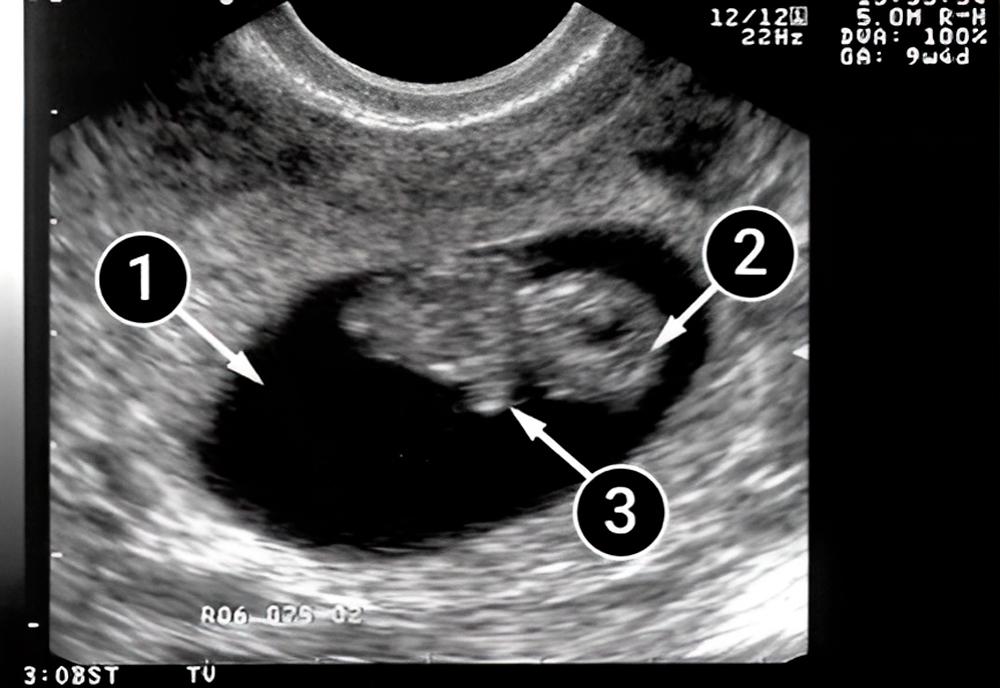

En la primera imagen, el óvalo grande y oscuro es el saco amniótico. Notemos la postura del bebé: está acostado con la espalda hacia la pared frontal del útero y podemos ver que su espalda se ha enderezado.

En esta etapa del embarazo, los huesos y los músculos esqueléticos del bebé se fortalecen. En esta imagen, sus brazos están presionados contra su pecho. Sus brazos siguen creciendo más rápido que sus piernas.

La cabeza del bebé se ve claramente y también se puede apreciar que se está haciendo más redonda.